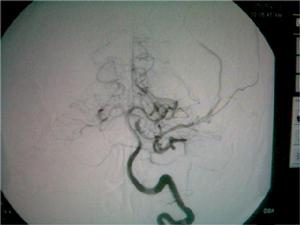

1.出血症狀發病前多數病人有情緒激動、用力、排便、咳嗽等誘因。發病突然,劇烈頭痛、噁心嘔吐、面色蒼白、全身冷汗。半數病人可出現精神症狀,如煩躁不安、意識模糊、定向力障礙等。以一過性意識障礙多見,嚴重者呈昏迷狀態,甚至出現腦疝而死亡。20%出血後有抽搐發作。有的還可出現眩暈、項背痛或下肢疼痛。腦膜刺激征明顯,常在蛛網膜下腔出血後1-2天內出現。多數病人出血後經對症治療,病情逐漸穩定,意識情況和生命體徵好轉,腦膜刺激症狀減輕。顱內動脈瘤在首次破裂出血後,如未及時適當治療,部分病人可能會再次或三次出現再出血者約占本病的1/3。2.腦神經損害以一側動眼神經麻痹常見,占6%-20%,提示存在同側頸內動脈-後交通動脈動脈瘤或大腦後動脈動脈瘤。

自發性蛛網膜下腔出血CT圖動脈瘤為最常見的出血原因大宗文獻統計表明動脈瘤出血占蛛網膜下腔出血病人的52%。此外,尚有一部分查不清死因者,其所占的比例受診斷條件影響,過去曾高達46.3%。隨著檢查手段的進步,對蛛網膜下腔出血的病因檢出率增加,不明原因的比例下降為9%~20%。血液病、顱內感染、藥物中毒等造成蛛網膜下腔出血者也偶見。

1.病因治療 蛛網膜下腔出血的根本治療。動脈瘤的直接夾閉不僅能防止再出血,也為以後的血管痙攣治療創造條件。